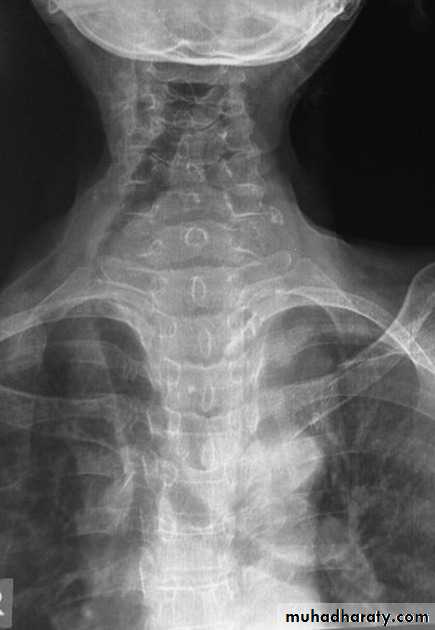

important note>>> density of the upper spine is more than density of the lower spine